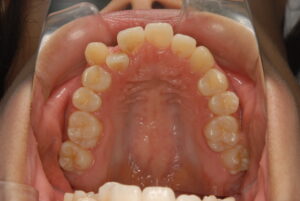

実際の症例紹介(20代女性/裏側ワイヤー矯正)

治療前

治療後

・主訴:八重歯と前歯の突出

・治療法:裏側からのワイヤー矯正(リンガル)

・治療期間:約1年半〜2年(目安)

・予想される副作用・リスク:装置装着後の違和感・疼痛、発音のしづらさ、一時的な咀嚼効率低下、ブラッシング不良によるむし歯・歯周病リスク など

※写真は代表的な症例です。口腔内の状態により治療法や期間は異なります。詳細は初診相談でご説明します。